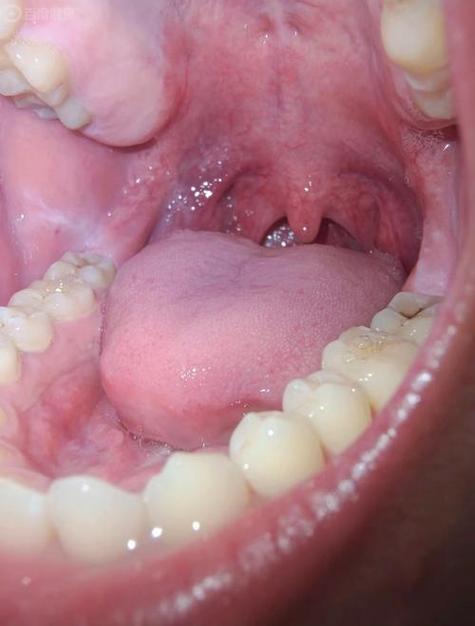

口腔扁平苔藓症状有哪些?

典型症状(口腔内的表现)

这是最核心的症状,主要发生在口腔黏膜的任何部位,最常见于颊黏膜(内腮帮子),其次是舌部、牙龈、唇部、硬腭等。

- 网纹型: 这是最典型的表现,黏膜上出现微小的白色或灰白色条纹,这些条纹交织成网状、树枝状或线状,像蕾丝花边一样,周围的黏膜可能正常或轻微发红。

- 丘疹型: 黏膜上出现针头大小、半透明的丘疹,散在或成簇分布,当这些丘疹融合成片时,就形成了网纹型。

- 斑块型: 出现界限清晰的、白色或灰白色的、稍高于黏膜表面的斑块,质地较硬,类似白斑,需要警惕癌变风险。

- 糜烂/溃疡型: 这是最严重、症状最明显的一种,在网纹或斑块的基底上,出现破溃、糜烂,形成浅表性的溃疡,患者会感到明显的疼痛,尤其在进食辛辣、酸性食物时加剧。

- 萎缩型: 黏膜变薄,呈鲜红色或暗红色,有时可以看到下面红色的血管,有时伴有白色条纹。

- 水疱型: 比较少见,黏膜下出现透明的小水疱,水疱破溃后也会形成糜烂面。

颜色

病变区域通常呈现白色、灰白色或珍珠色,这是由于黏膜下固有层中的炎症细胞浸润,使上皮角化过度所致。